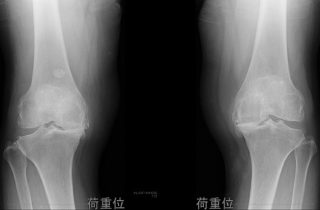

Many patients, case reportsいろんな患者さん、症例報告